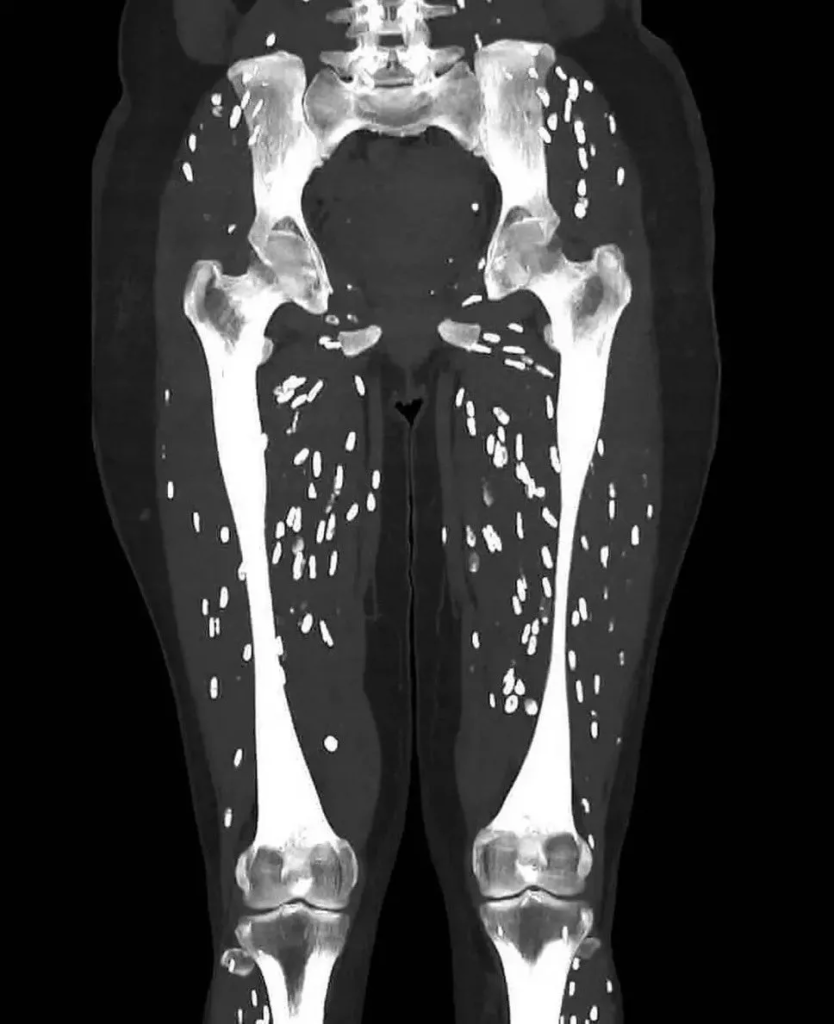

An emergency room doctor in Florida recently shared a case that stopped him in his tracks. First, Dr. Sam Ghali posted a CT image on X that showed a patient’s legs dotted with countless tiny bright spots. Then he invited his followers to guess the cause, as he often does to teach the public about medical emergencies.

Soon after, he shared the diagnosis. The patient had cysticercosis, a parasitic infection linked to the pork tapeworm, Taenia solium. People can pick it up when they eat undercooked pork that contains tapeworm cysts. Those larvae can pass through the intestinal wall, enter the bloodstream, and spread through the body. Doctors sometimes call the scan pattern “rice grain” calcifications because the specks can look like small grains in the muscles.